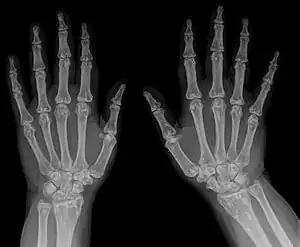

Diagnostic methodX-ray, ultrasound[4]

The diagnosis of this condition can be ascertained via several techniques one such method is genetic testing, as well as:[3][4]

• X-ray

• Ultrasound